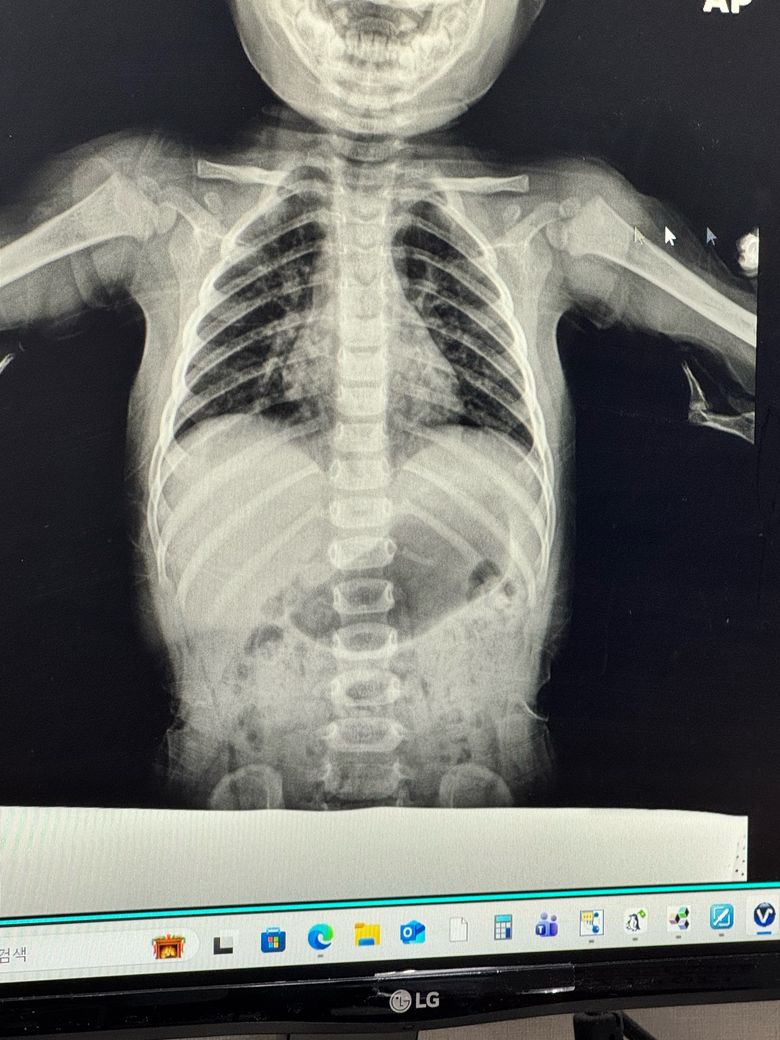

아기 폐사진 봐주세요 폐렴인지 궁금합니다

오늘 폐 엑스레이 찍고 왔는데

폐렴인지 봐주세요..! ㅠ

폐렴으로 보이시는지 아님 단순 기관지염으로 보이시는지 궁금합니다

사진 한 장만으로 확진은 어렵지만, 전형적인 폐렴 소견(국소적으로 하얗게 뿌옇게 보이는 폐음영 증가, 일측성 침윤)이 뚜렷하게 보인다는 인상은 비교적 약해 보입니다.

다만 다음과 같은 점은 기관지염·모세기관지염에서 자주 보이는 패턴입니다.

1. 양쪽 폐문(가운데 부위) 주변이 약간 흐리게 보임

2. 전반적으로 공기량이 조금 많아 보이는 듯한 인상

3. 특정 부위만 하얗게 뭉친 폐렴 패턴은 분명하지 않음

즉, 영상만 보면 ‘전형적인 폐렴’보다는 ‘바이러스성 기관지염/모세기관지염’ 쪽 가능성이 더 흔한 모습입니다.